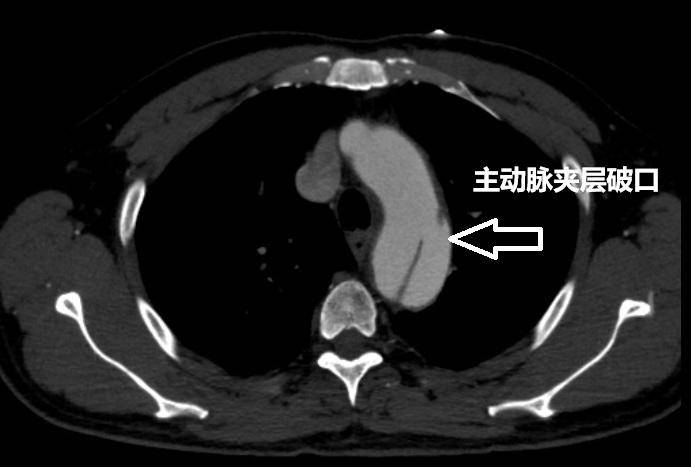

“进一步检查发现,患者王先生当时的主动脉从左锁骨下动脉一路撕裂至左髂动脉,累计长度已近40厘米,影响到多器官供血血管。”卢惟钦说。

▲患者术前主动脉夹层检查影像 受访医生供图

主动脉是人体最粗大且直接连接心脏的血管,压力极高。而所谓主动脉夹层,实际上是一种常见的心血管疾病,但危险性极高。卢惟钦告诉红星新闻:“主动脉夹层即血管壁内膜撕裂,血液冲入中层形成‘真假两腔’,一旦外膜破裂会引发大出血,死亡率极高。”

卢惟钦介绍,主动脉夹层是一种极为危险的心血管疾病,通常又被称为“血管炸弹”。他用通俗的话向记者解释,人的血管实际分为三层,当血压过高时,就可能导致血管中薄弱的一层破损,而血液一旦涌入破损的一层,就会与未破损血管层形成夹层,也即主动脉夹层。